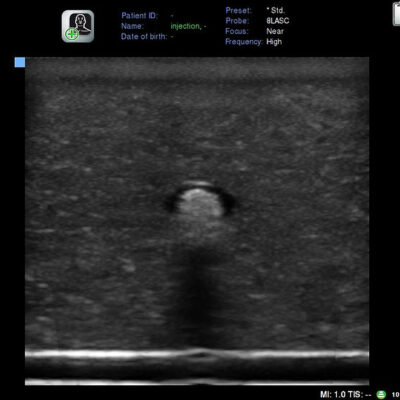

INTERNAL LANDMARKS : Nerve

INJECTION CHARACTERISTICS

Tissue: <5 PSI for fluid flow to occur. Intraneural: >20 PSI for fluid flow to occur